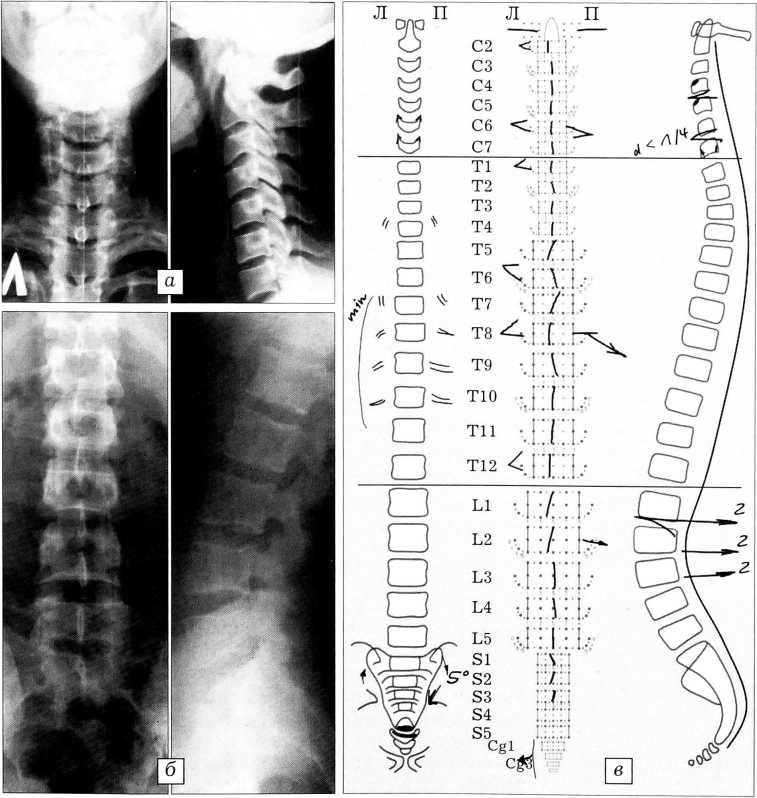

Больной М.,31 года, обратился с жалобами на боли в шее и пояснице, периодически возникающие головные боли, онемение левой руки по утрам. Пациент занимается преимущественно умственным трудом, водит автомобиль, травм не было. При системном анализе рентгенограмм позвоночника (рис. 2) диагностировано локальное искривление позвоночного столба на уровне Т7-11 влево. Крестец скручен вправо на 5°, а копчик — влево. Позвонки С6, Т8, L2 имеют боковой наклон вправо. Остистые отростки большинства позвонков занимают центральное положение, однако у позвонков С6, Т1, Т8 и Т12 они смещены влево, оставаясь параллельными оси базового отвеса. Аксис, а также С2, С6, Т1, Тб, Т8 и Т12 позвонки ротированы влево.

Рис. 2. Больной М. Рентгенограммы шейного (а), поясничного (б) отделов и графическая часть индивидуальной карты системного анализа рентгенограмм позвоночника (в).

На рентгенограммах в боковой проекции шейный лордоз выпрямлен. Отмечается симптом распорки на уровне С4-5, С6-7, L1-2. Грудной кифоз от Т2 до Т12 в пределах нормы (до 40°). Поясничный лордоз обычной формы на уровне L2-5 и уплощен на уровне L1-2. Имеет место задний спондилолистез L1, L2 и L3 позвонков.

Диагностированы скошенность передних отделов тел позвонков С4 и С5 и сужение межпозвонковой щели С6-7, которые являются начальными признаками остеохондроза. Констатированы проявления артроза суставов: дугоотростчатых во всех трех отделах, реберно-позвоночных Т4, Т7-10 с обеих сторон, правого крестцово-подвздошного, крестцово-копчикового и полулунных суставов С6 и С7 позвонков. Обнаружена врожденная аномалия развития — вазообразная форма тела С7 позвонка, обусловившая нарушения статики и, по-видимому, ставшая причиной дегенеративно-дистрофических изменений шейного отдела позвоночника.

Заключение: левосторонний сколиоз грудного отдела I степени. Симптом распорки С4-5, С6-7, L1-2. Ретролистез L1, L2, L3. Остеохондроз шейного отдела. Артроз дугоотростчатых, реберно-позвоночных, правого крестцово-подвздошного и крестцово-копчикового суставов, ункоартроз. Вазообразная форма тела позвонка С7.

Данный клинический пример иллюстрирует возможности метода САРП для отражения многочисленных минимальных нарушений статики отдельных позвонков трех отделов позвоночника, приведших к дегенеративно-дистрофическим изменениям.